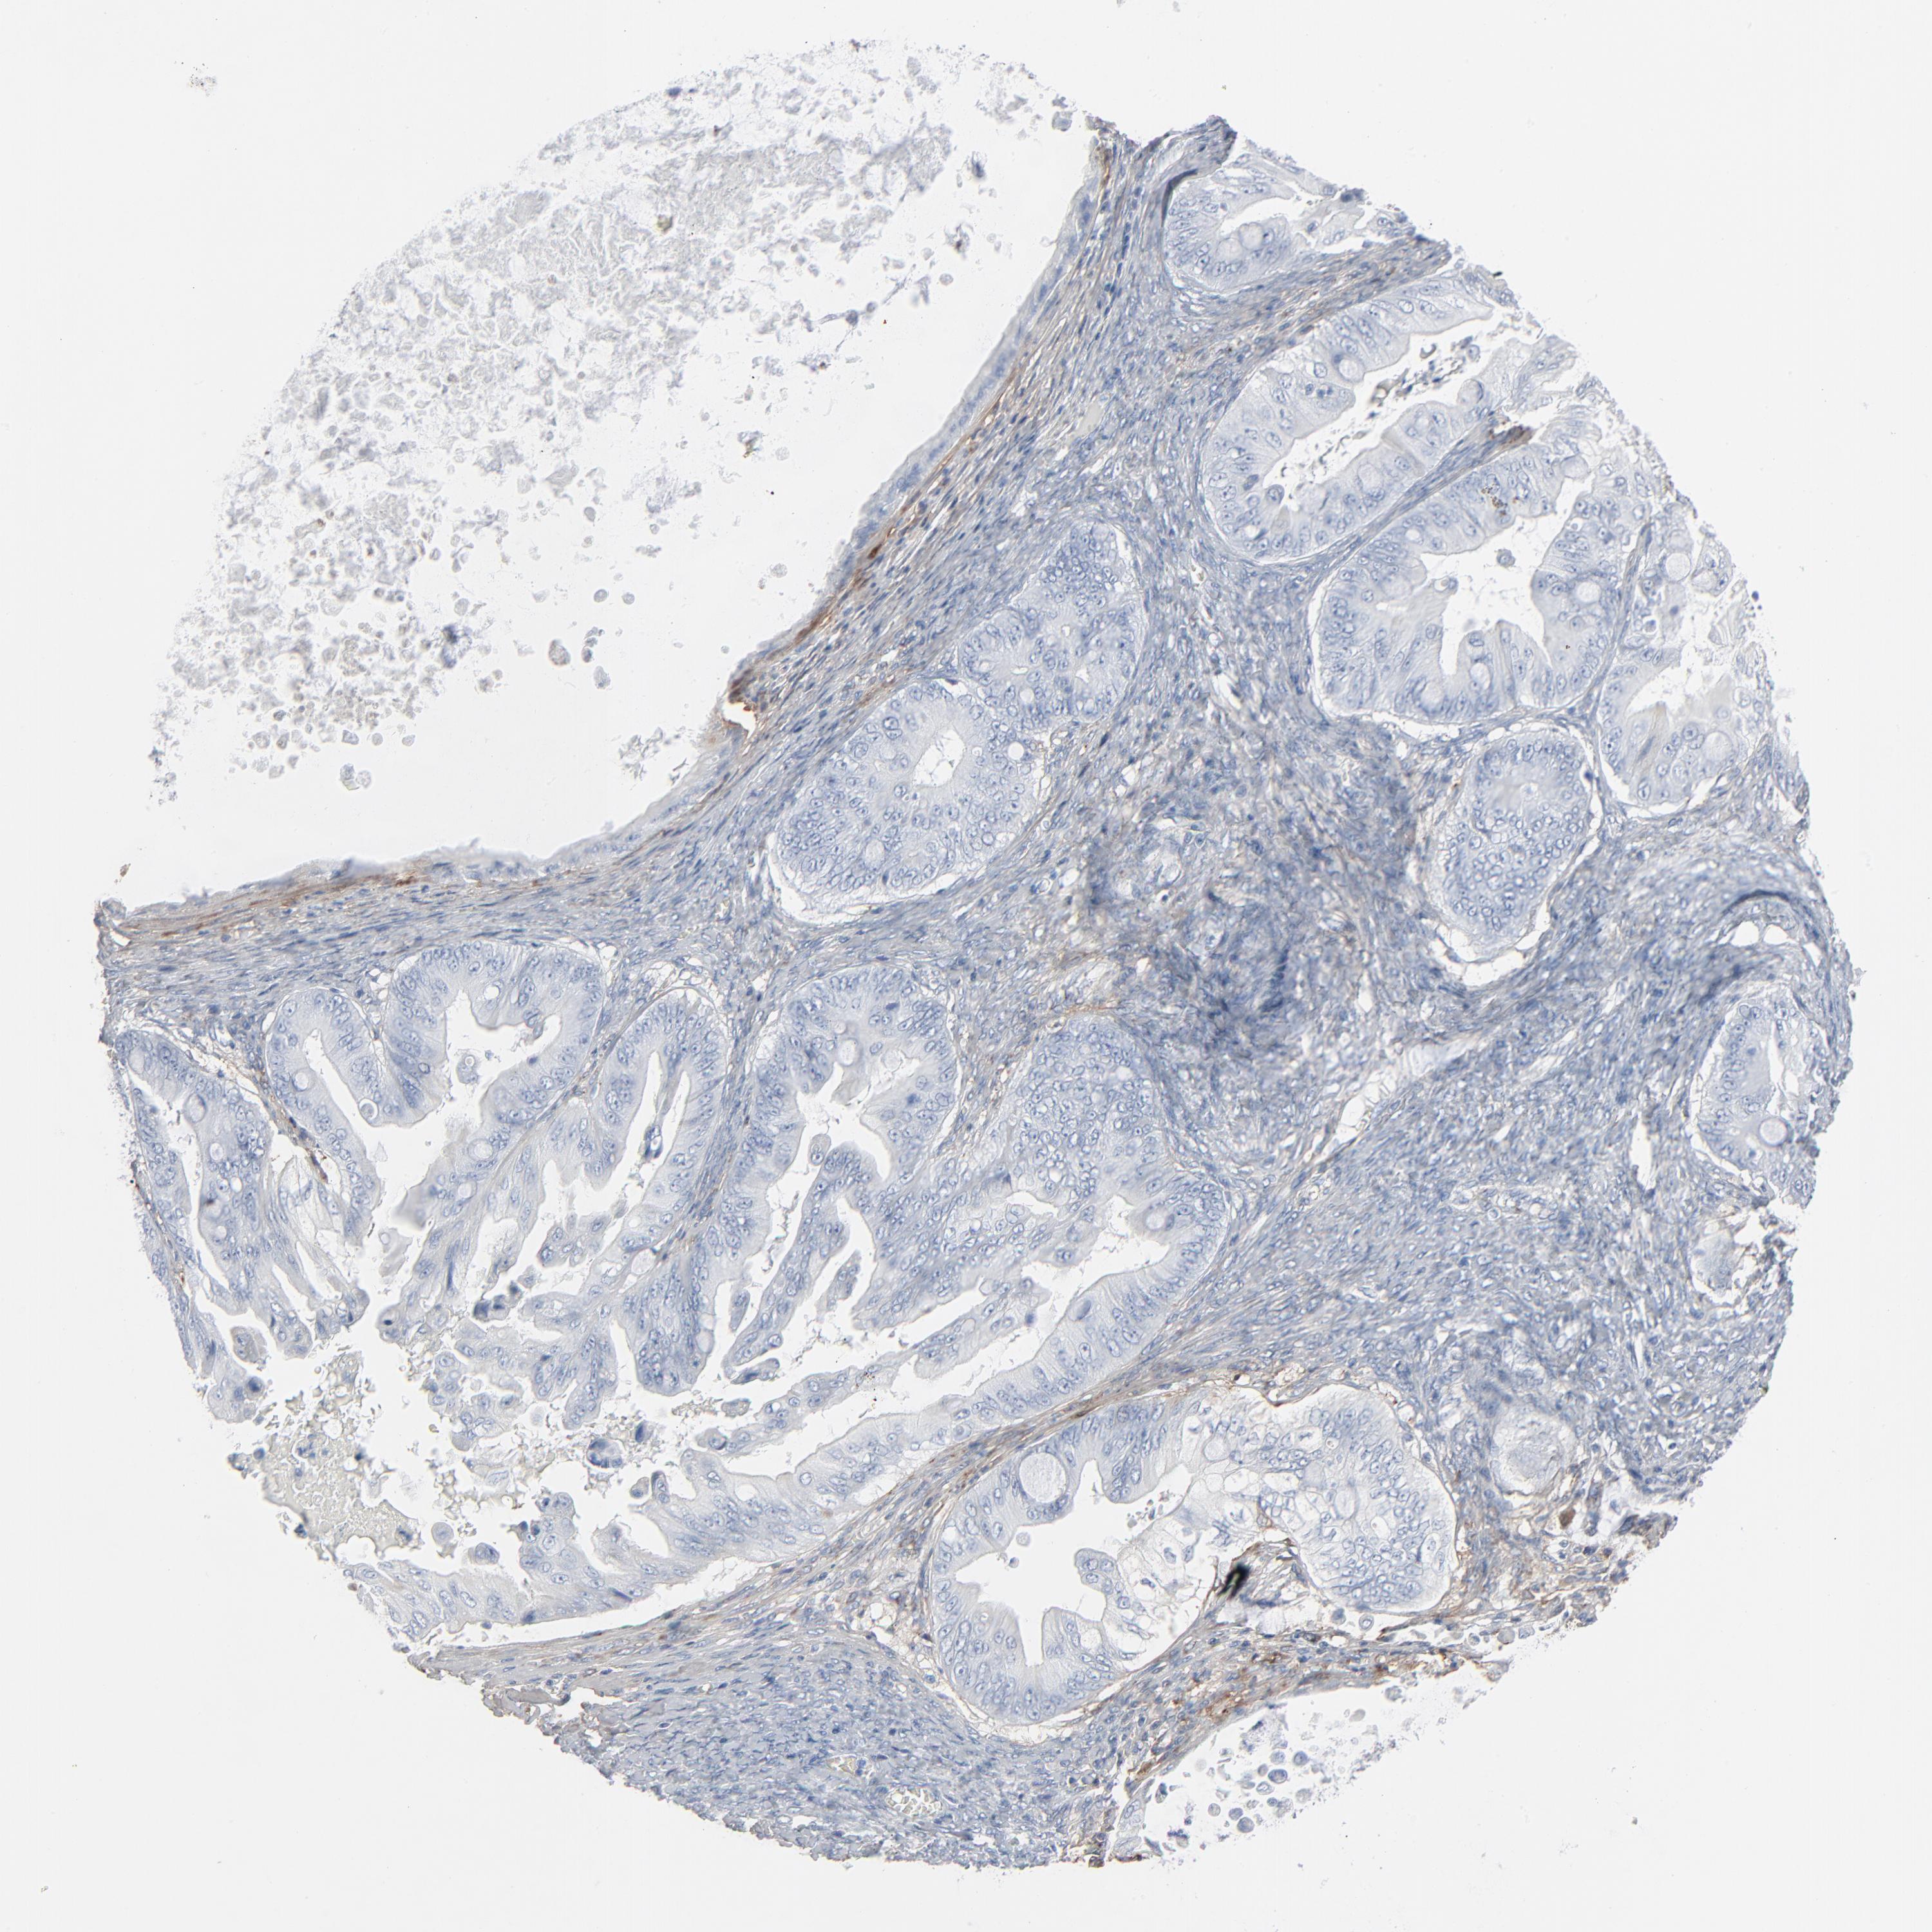

OVARIAN CANCER - Protein expressioni

A mouse-over function shows sample information and annotation data. Click on an image to view it in a full screen mode. Samples can be filtered based on level of antibody staining by selecting one or several of the following categories: high, medium, low and not detected. The assay and annotation is described here.

Note that samples used for immunohistochemistry by the Human Protein Atlas do not correspond to samples in the TCGA dataset.

Antibody stainingi

Antibody staining in the annotated cell types in the current human tissue is reported as not detected, low, medium, or high, based on conventional immunohistochemistry profiling in selected tissues. This score is based on the combination of the staining intensity and fraction of stained cells.

Each image is clickable and will lead to virtual microscopy that enables deeper exploration of all samples and also displays staining intensity scores, fraction scores and subcellular localization as well as patient and tissue information for each sample.

Antibody HPA003157

Antibody CAB003678

Staining

High

Medium

Low

Not detected

Intensity

Strong

Moderate

Weak

Negative

Quantity

>75%

75%-25%

<25%

None

Location

Nuclear

Cytoplasmic/membranous

Cytoplasmic/membranous,nuclear

Carcinoma, endometroid

Cystadenocarcinoma, serous, NOS

Cystadenocarcinoma, mucinous, NOS